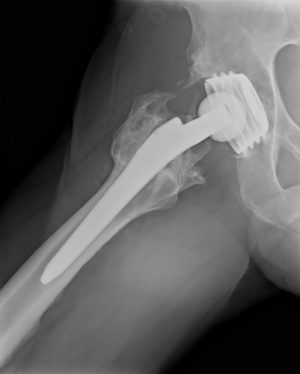

- Замена тазобедренного сустава – протез позволяет восстановить все утраченные возможности, связанные с функциями тазобедренного сустава.

- Замена плечевого сустава – операция по замене всего сустава плеча или отдельных его элементов.